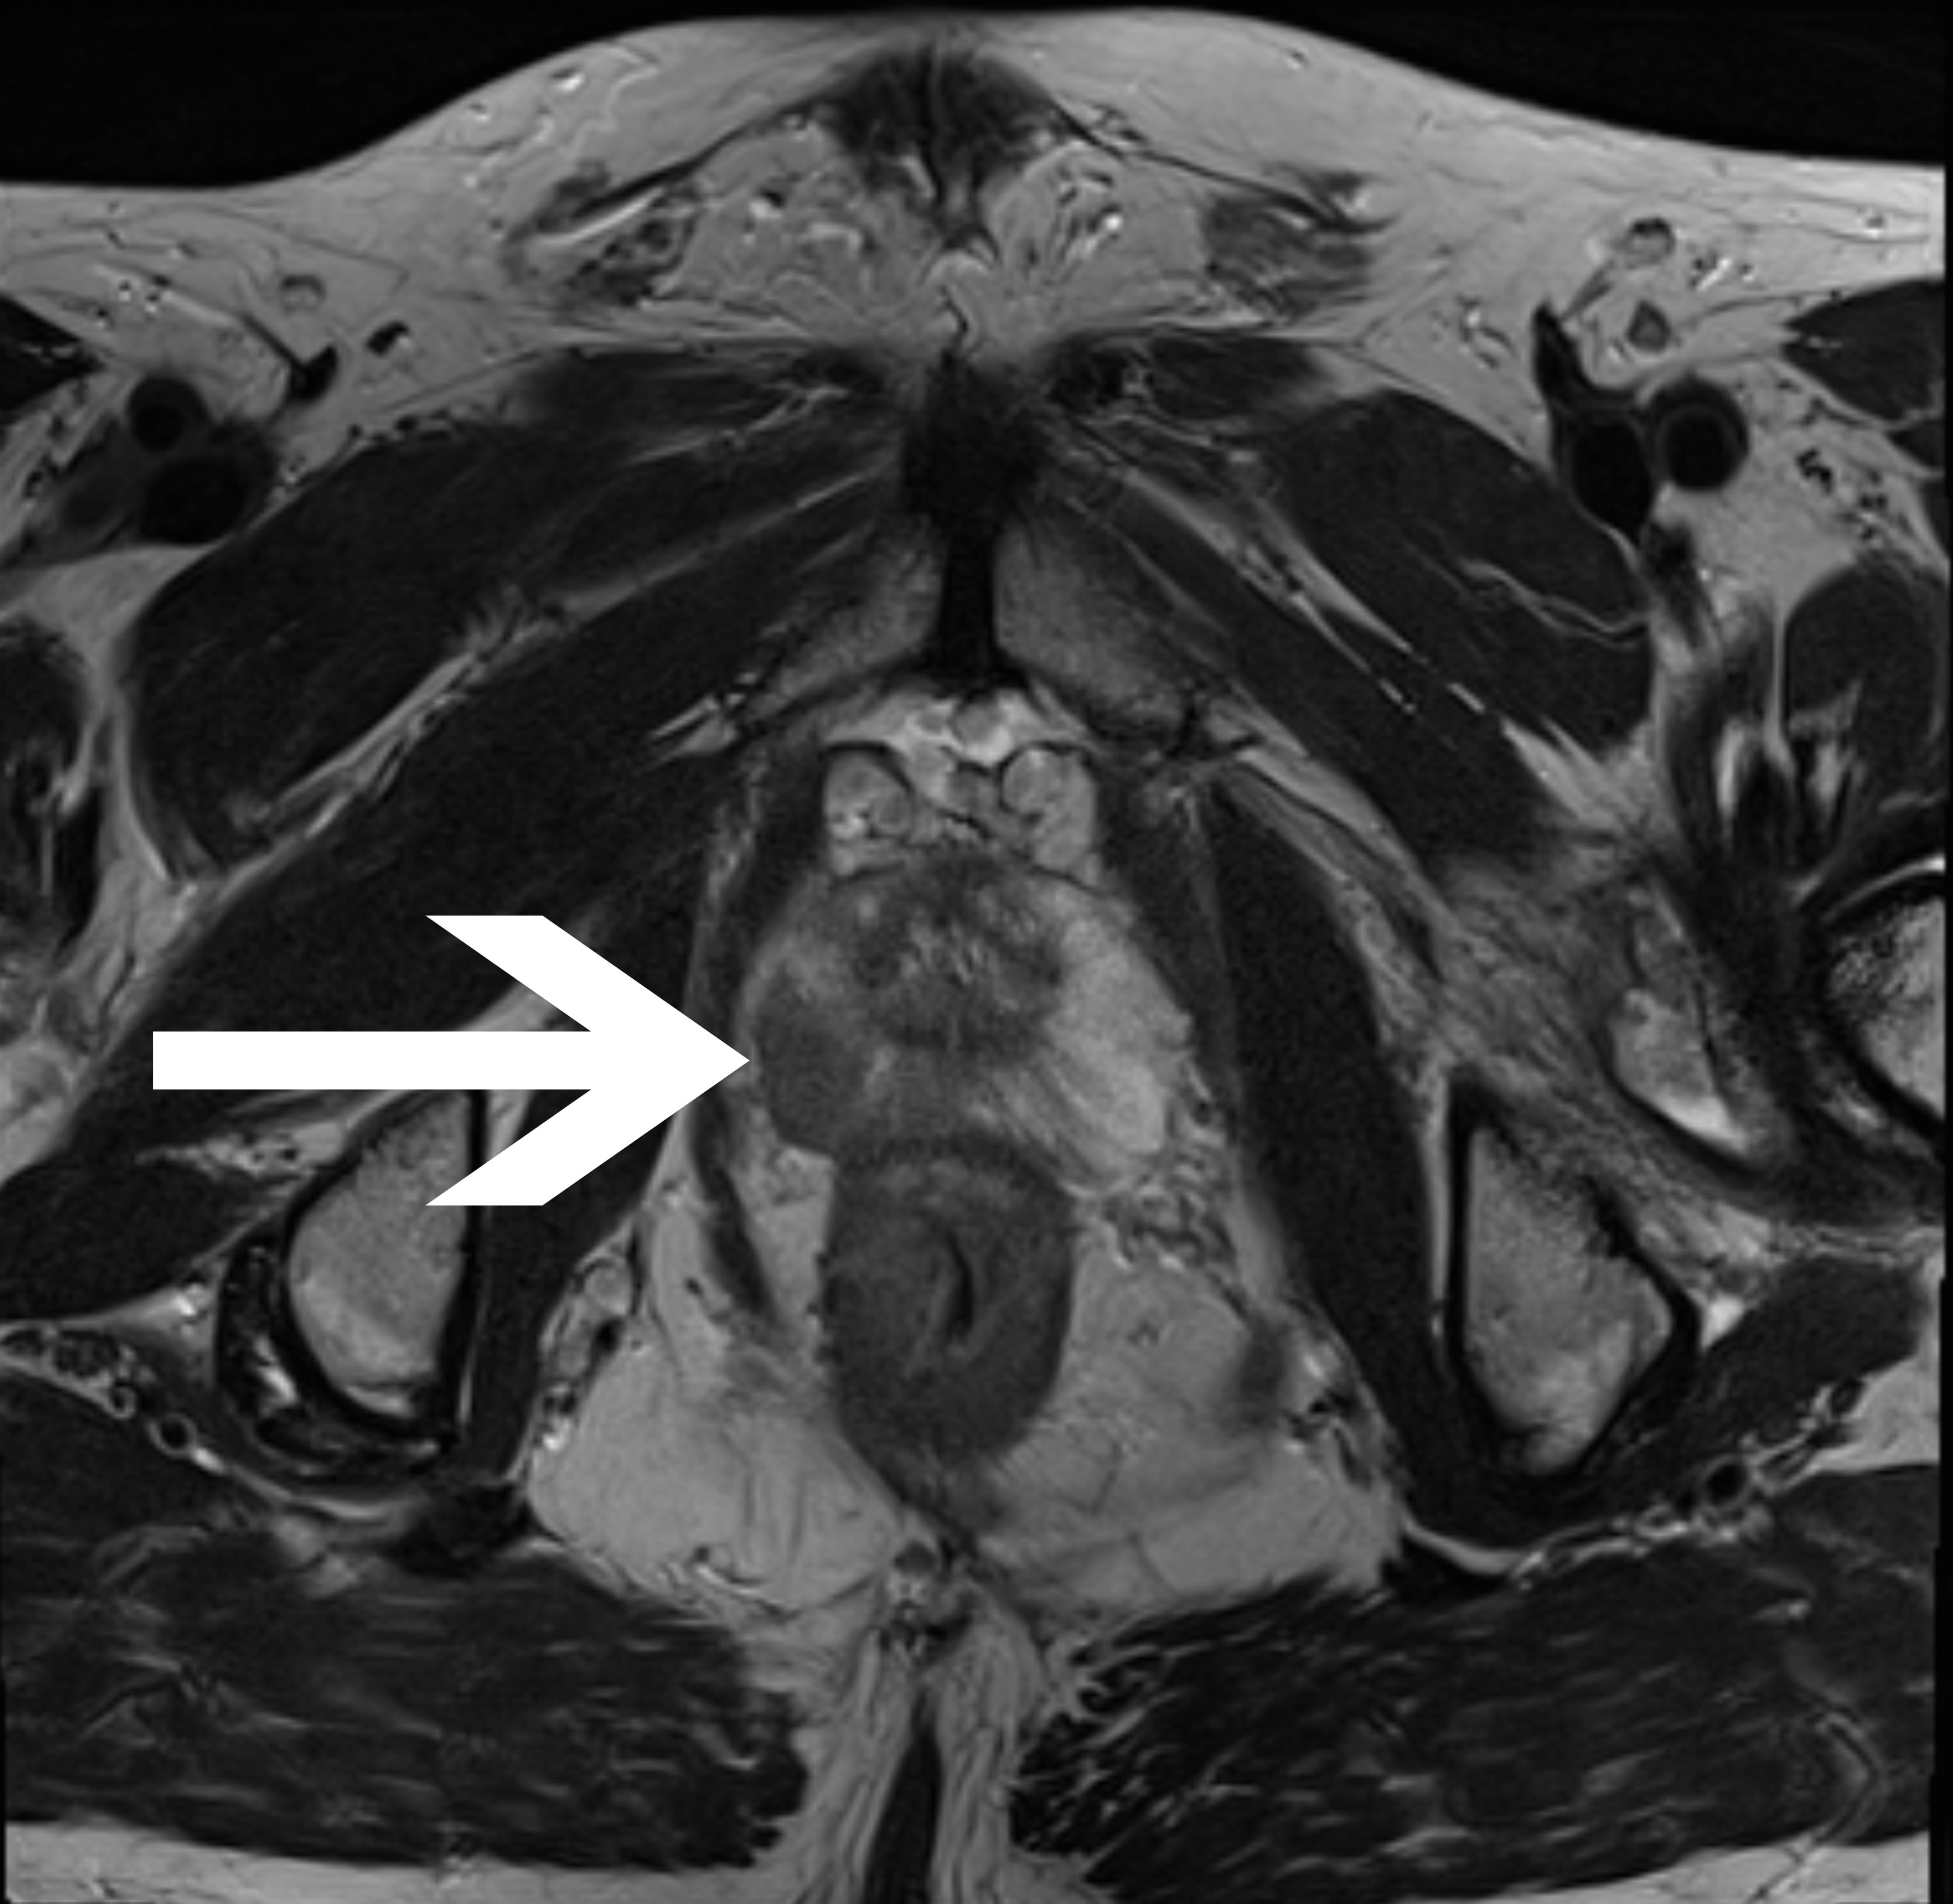

b

Abb1:

Histologisch gesichertes einseitiges

Prostatakarzinom in der

peripheren Zone rechts in:

koronar (Abb.1a) und transversal (Abb.1b)

ausgerichteter T2-TSE-Sequenz.